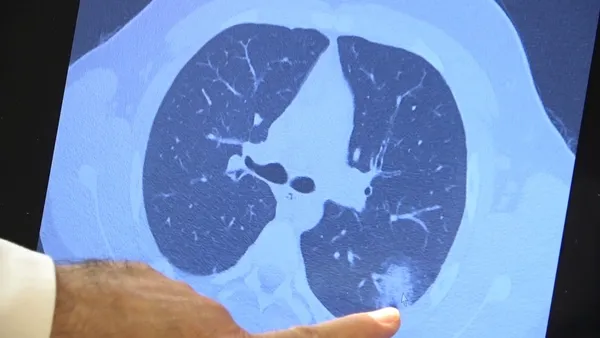

14 yaşında, kronik rahatsızlığı olan ve akciğerlerinde tahribattan dolayı ciddi öksürük, ateş ve nefes darlığı çeken bir hastanın akciğerlerini inceleyen Prof. Dr. Özkaya, "14 yaşındaki kronik rahatsızlığı mevcut olan bir genç hastamızda ciddi akciğer tutulumları var. Her iki akciğerinde de yaygın buzlu cam ve konsolidasyon alanları var. Bu yaştaki çocuklarda beklemediğimiz bir durumdur. Okullarımızda da bu risk var. Okullarımızın açık kalmasının ve sağlık sistemimizin kitlenmemesi için mutlaka aşı olmalıyız. Çocuklarımıza rol model olmalıyız. Şu anda hastanelerimiz hastalara yetişebiliyor. Yatak sayımız yeterli. Ancak kontrollü sosyal hayatımızı düzene sokmadıkça ve aşı olmadıkça, gelecekte hastanelerde yatak sayısı sıkıntısı çekebiliriz" dedi.